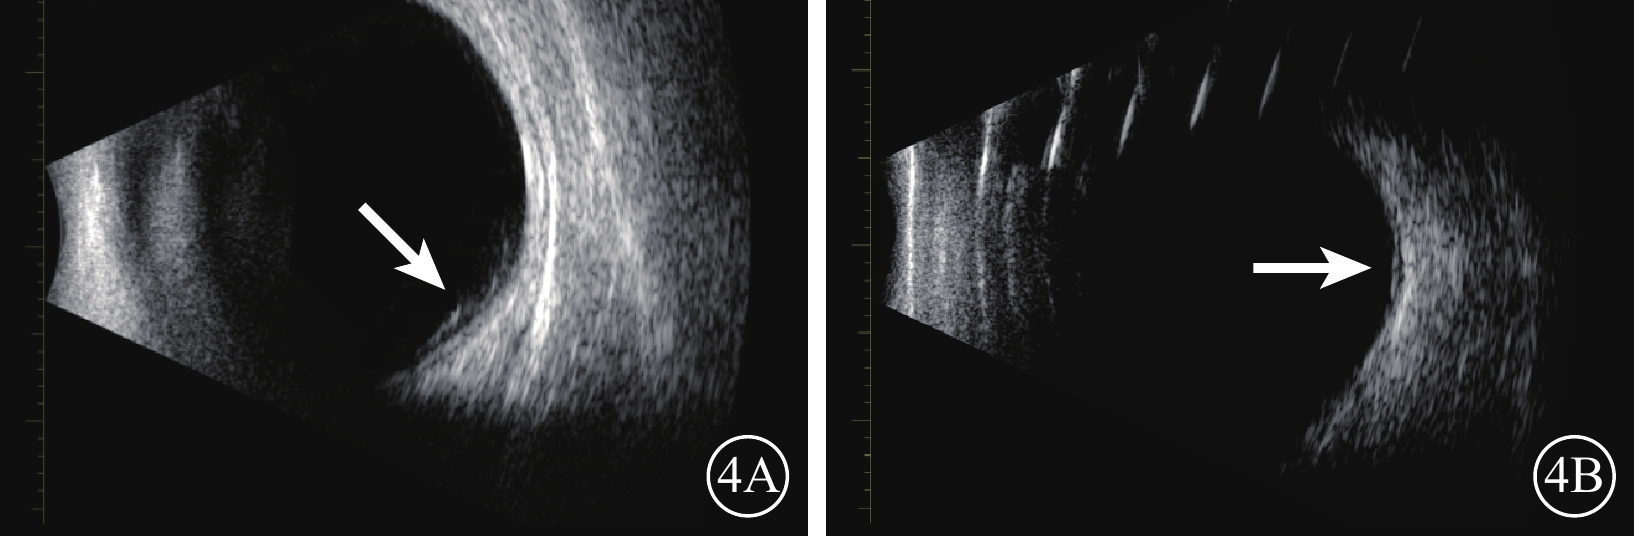

以上是體外實驗結果,雖然不能完全模擬人眼,但也能說明問題。遺憾的是,本研究材料為無色透明,不能直接從眼底觀察到,但體內研究手術后2周B型超聲檢查顯示較為清晰(圖4)。對于何時移位和降解的問題,基于體內外研究和高眼壓發生的時間,我們推斷降解和移位這一過程是逐漸進行的,考慮到覆蓋視網膜裂孔的量很小,在眼內持續的具體時間不好量化,后期設計加入可以顯色的材料更為直觀。